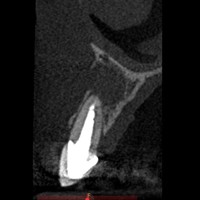

Po urwaniu narzędzia w zębie, endodonta odstąpił od leczenia kanałowego. Wykonano resekcję. Na RTG widoczne dobre gojenie tkanek kostnych, niewidoczna blizna na dziąśle.